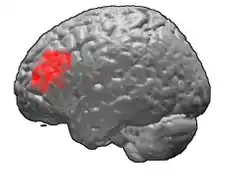

Brodmann area 46, or BA46, is part of the frontal cortex in the human brain. It is between BA10 and BA45.

BA46 is known as middle frontal area 46. In the human brain it occupies approximately the middle third of the middle frontal gyrus and the most rostral portion of the inferior frontal gyrus. Brodmann area 46 roughly corresponds with the dorsolateral prefrontal cortex (DLPFC), although the borders of area 46 are based on cytoarchitecture rather than function. The DLPFC also encompasses part of granular frontal area 9, directly adjacent on the dorsal surface of the cortex.

Cytoarchitecturally, BA46 is bounded dorsally by the granular frontal area 9, rostroventrally by the frontopolar area 10 and caudally by the triangular area 45 (Brodmann-1909). There is some discrepancy between the extent of BA8 (Brodmann-1905) and the same area as described by Walker (1940).[1]

Animation.